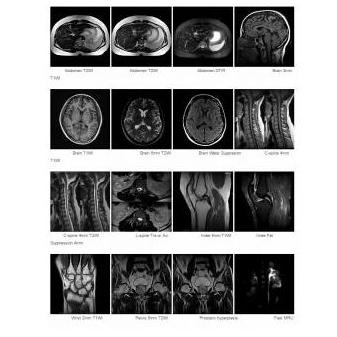

Rezonans magnetyczny MRI OPENMARK III 0.3T

Rezonans magnetyczny OPENMARK III 0.3T posiada konstrukcję otwartego magnesu w kształcie litery C, co daje większy komfort pacjentom podczas badania. Aparat dostarcza wysokiej jakości obrazy, zawiera wiele protokołów ustawiania presetów, jak również zaawansowanych aplikacji, takich jak obrazowanie dyfuzji, ultraszybkie obrazowanie, angiografia czy skanowanie na wstrzymanym oddechu.

• Platformy: sprzętowa i programowa zapewniają szybkie skanowanie, dając przy tym wysoką jakość obrazu oraz dostęp do zaawansowanych funkcji obrazowania.

• Bogata sekwencja skanowania, zaawansowana technologia przetwarzania obrazu i post-processingu zapewniają wysoką jakość obrazu.

• Wiele aplikacji, zaspokajających potrzeby kliniczne.